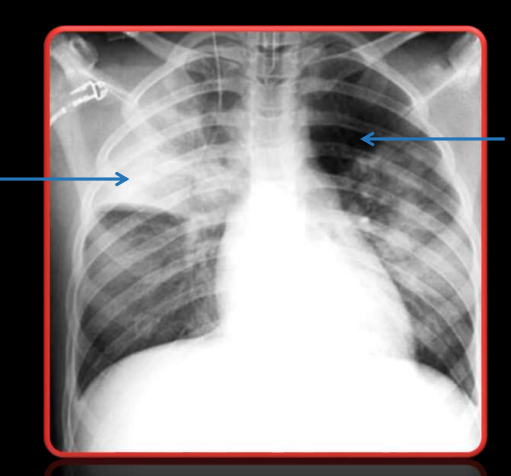

<p>Indica la nomenclatura de la flecha izquierda y derecha, respectivamente:</p>

Indica la nomenclatura de la flecha izquierda y derecha, respectivamente:

Radiopáco, Radiolúcido